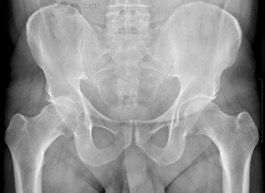

2. Restoring anatomy

Restoring the patient’s preoperative anatomy is a fundamental goal of total hip arthroplasty, applying equally to limb length, femoral offset and rotation centre of the hip. Of course, there are certain cases (dysplasia, congenital dislocation) in which we must sometimes accept a compromise, and we will return to this. The anatomy of each patient is individual [1, 2]. The neck-shaft angle, femoral offset, length and femoral version are amongst the proximal femur parameters that differ from one patient to another, and we must look to restore them as faithfully as possible. The best reproduction possible of these parameters results in a restoration of tension to the abductor muscles and lateral rotators, ensuring improved post-operative recovery [3] while reducing the risk of post-operative complications, especially instability.

Femoral offset

The anatomical positioning of short stems along the medial cortex will also allow for restoration of femoral offset. Most of the time this is an advantage over straight stems even in “standard” hips, as it is in some specific cases.